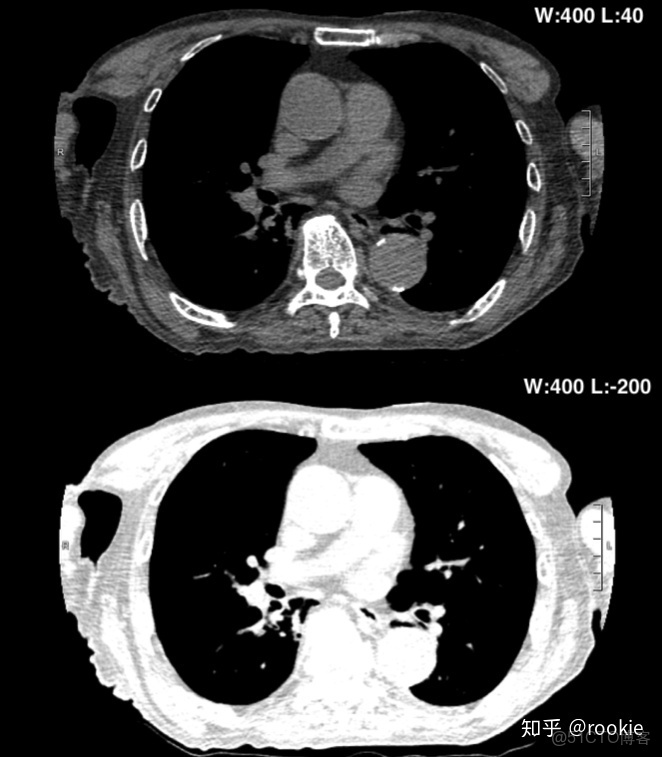

上面的圖像顯示了增加窗口寬度將如何降低圖像的對比度。與下窗格相比,頂部窗格的窗口寬度更小,皮下組織中的肌肉和脂肪之間的對比更加明顯。

上圖演示了降低窗口水平如何增加圖像亮度。頂部窗格具有更高的窗口水平,在窗口寬度內包含密度的組織比底部窗格中的組織要暗得多。